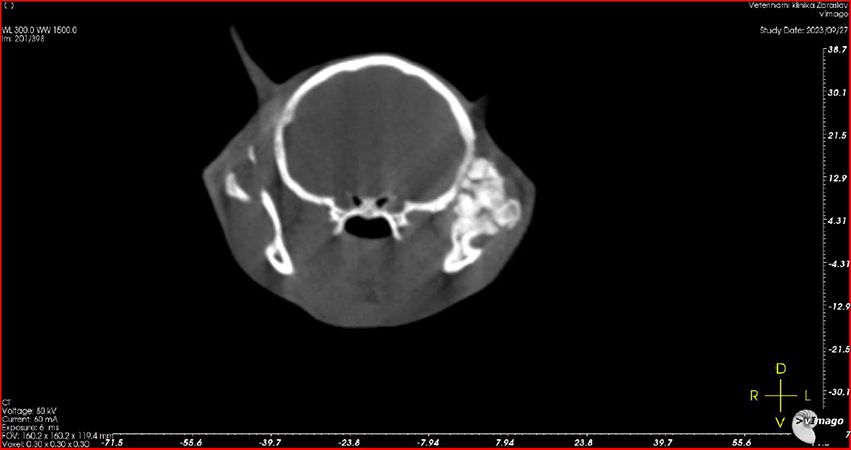

27.9.2023

Leo absolvuje nové CT vyšetření. Je zřejmé, že oproti původní diagnóze (špatně zhojené poškození měkkých tkání), je z nových snímků jasně patrné, že Leo má špatně zhojenou zlomeninu spojení spodní čelisti a podočnicového oblouku na levé straně, což je důvod, proč se mu pusinka opět zavřela. Je nutná operace. Po krátké konzultaci v Nuslích Linda domlouvá, aby Lea odoperovali akutně na Zbraslavi. Dostává zprávu, 3D model i CT snímky do mailu.